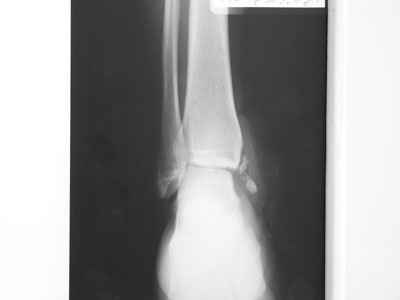

Уважаемые коллеги! Помогите определиться с тактикой лечения больной 50 лет! Травма в результате ДТП 1 января 2011г. открытый многооскольчатый перелом медиальной лодыжки левого голеностопного сустава со смещением. При поступлении в области медиальной лодыжки поперечная рана 5,0х1,0 см. сильно загрязнена, была выполнена ПХО. 05.01.2011г. сняты все швы по поводу нагноения раны, выполнена некрэктомия нежизнеспособных краев раны. На сегодня голеностопный сустав незначительно отечен, слегка болезнен при пальпации в области медиальной лодыжки. Температура тела нормальная, боли практически нет. Кровь спокойная. В области медиальной лодыжки имеется ранка округлой формы до 0,3 см., со скудным гнойным отделяемым (следы на салфетке после перевязки 1 раз в 2 дня). Посев из раны выполнить невозможно. На последних контрольных рентгенограммах признаки остеомиелита медиальной лодыжки? Помогите определиться с тактикой лечения: оперативное? Консервативное? С уважением Александр Белоконь!

4 недели после травмы - это еще пока открытый срастающийся инфицированный перелом, а не остеомиелит. Что касается рентгенограмм - в таком разрешении трудно оценить структуру кости.

Уважаемые коллеги! Прошу прощения за собственную невнимательность. У больной травма не 1 января 2011г., а 1 декабря 2010г., т.е. уже 2 месяца.

Прилагаю данные фистулогрфии. Основной вопрос, все же, лечить консервативно или оперативно? Если оперативно, то какой объем? А что если прийдеться резецировать всю медиальную лодыжку!?